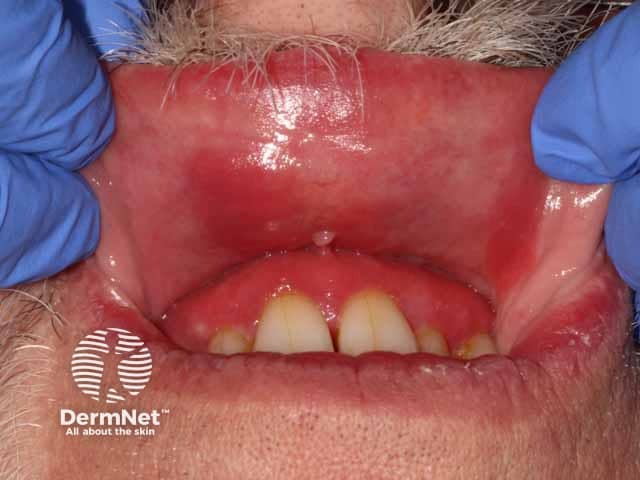

Red, glazed and oedematous changes on the hard palate in plasma cell mucositis (PCM-patient2)

Plasma cell mucositis most commonly affects the oral mucosa and gingiva. Although it is typically painful with potential oral and oropharyngeal functional consequences, it can also be asymptomatic.